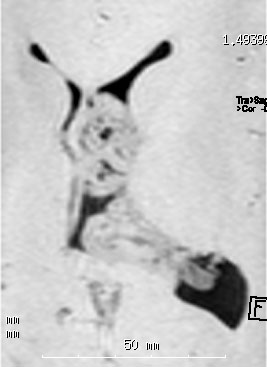

20代の男性の神経細胞腫です。側脳室の中のとても大きな腫瘍です。上段はガドリニウムという造影剤を入れた時のMRIです。下段の中央はCTですが,石灰化が見られます。脳外科の先生には,この脳室内腫瘍は一見transcallosal approach(経脳梁到達法)という手術で取れるように見えるかもしれませんが,そうではなくて,脳室の壁とくに上壁と側壁にくっついているのでなかなか取れません。この患者さんの場合は右の頭頂葉というところからtranscortical approach(経皮質到達法)で全摘出しました。後遺症もなく再発もなく術後10年が過ぎています。全部とれれば治ってしまう腫瘍です。

無症状で見つかった小さいcentral neurocytomaのCT像です

- CTでは石灰化 (50%) がみれますし,MRIではのう胞が見られて(80%) 造影剤で白く増強(全例)されます